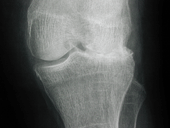

Jedes Gelenk ist eine funktionelle Einheit und besteht zusätzlich zur knöchernen Verbindung aus dem Gelenkknorpel, der Synovialmembran und der Gelenkflüssigkeit. Damit eine gleichmäßige Belastung auf das Gelenk trifft, verteilen Muskulatur und Gelenkkapsel die auftretenden Kräfte und unterstützen die Ernährung des Gelenkknorpels. Der Knorpel fängt die Kräfte auf und wirkt wie ein Stoßdämpfer und durch die glatte Oberfläche und die Synovialflüssigkeit wird ein reibungsloses Gleiten der Gelenkflächen aufeinander sichergestellt.

Im Knorpel des Erwachsenen finden sich weder Blut- oder Lymphgefäße noch Nervenendigungen. Die Ernährung findet als Diffusion vom Gelenkspalt aus statt, wobei die intermittierende Druckbeanspruchung eine wichtige Rolle spielt. Die von der Synovialmembran gebildete Flüssigkeit enthält unterschiedliche Bestandteile zur Ernährung des Knorpels und entsorgt auch die Endprodukte des Knorpelstoffwechsels. Vor besonderer Bedeutung ist hierbei die Hyaluronsäure, die als hochmolekulares Biopolymer Glukuronsäure und N-Acetyl-Glukosamin enthält. Diese Stoffe wirken entscheidend an der Knorpelbildung und – struktur mit, wobei die Proteine nur eine bestimmte Anordnung der Bausteine zulassen. Die Hyaluronsäure ist extrem hydrophil und bindet sehr viel Wasser. Dadurch wird der Knorpel zu einer elastischen Struktur, die unter Belastung Flüssigkeit abgibt und nach der Belastung ihre ursprüngliche Struktur wieder einnimmt. Für die Viskosität und die Schmierstoffeigenschaften der Synovialflüssigkeit ist ebenfalls in hohem Maße die Hyaluronsäure verantwortlich.

Veränderungen des Knorpels treten mit dem Alter auf, weil die Aktivität und der Stoffwechsel der Knorpelzellen nachlässt. Dadurch wird der Knorpel spröde. In der Synovialflüssigkeit wird der Eiweißgehalt geringer und die Viskosität nimmt ab. Damit ist eine zunehmende Degeneration des Knorpels verbunden, der anfälliger für Verletzungen wird. Ist der Knorpel geschädigt, bildet er sich zunächst zurück und wird im Verlauf der Reparatur durch faserigen Ersatzknorpel ersetzt. Dieser Knorpel ist weniger belastbar und fördert die degenerativen Veränderungen. Neben zunehmendem Lebensalter sind auch vermehrtes Körpergewicht oder eine angeborene Fehlstellung sowie Sportverletzungen ein Risikofaktor für Gelenk-Knorpelschäden.

Es kommt zu Schmerzen des Gelenks, die Beweglichkeit ist eingeschränkt und nicht selten bildet sich ein Erguss im Gelenk, der das Schädigungsmuster zusätzlich fördert. Therapeutisch kann durch Wärme- oder Kälteanwendung, durch medikamentöse Maßnahmen mit Schmerzstillung und Entzündungshemmung die Symptomatik gebessert werden. Bei schweren Schmerzen werden opioidhaltige Schmerzmittel angewendet, Kortison dient der Entzündunghemmung und in therapieresistenten Fällen kann eine Operation erforderlich werden, um den Knorpelschaden zu beheben.

Als therapeutisch wirksame Substanzen bei Knorpelschädigung werden Glucosaminsulfat oder Hyaluronsäure verwendet, die dazu beitragen, dass die Gelenkarthrose gebessert und die Knorpeldefekte ausgebessert werden. Bei altersbedingter Degeneration des Knorpels, der klassischen Ursache für eine Arthrose, soll der Knorpelabbau aufgehalten und möglichst wieder hergestellt werden. Wird z.B. Hyaluronsäure in das Gelenk injiziert, werden wichtige Bestandteile zum Knorpelaufbau in die Synovialflüssigkeit gebracht, die einerseits die Reibung im Gelenk verhindern und auf diesem Weg die Beschwerden bessern soll, andererseits durch wichtige Bausteine für den Wiederaufbau des Knorpels in den pathophysiologischen Prozess der Degeneration eingreifen.